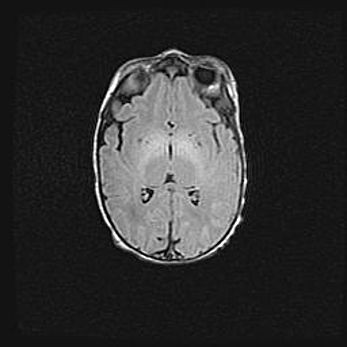

Наружная гидроцефалия с возможной атрофией височных областей.

Возраст: 28 дней

Вес: 3670 г

Пол: мужской

Окружность головы: 38 см

Срок гестации: 40 недель

Гидроцефалия головного мозга у новорожденных – это заболевание, которое характеризуется скоплением избыточного количества спинномозговой жидкости в желудочковой системе головного мозга в результате затруднения её перемещения от места выработки к месту поглощения в кровеносную систему или вследствие нарушения абсорбции. При открытой наружной форме гидроцефалии у новорожденных расширяются и переполняются субарахноидные пространства.

При нормотензивных  формах,  которые,  как  правило,  являются  следствием  перенесенных ишемических  повреждений  паренхимы  мозга,  возможно  сочетание микроцефалии  с нормотензивной гидроцефалией. В основе данных изменений лежит атрофия больших полушарий с преимущественной  локализацией  в  лобно-височных  областях.